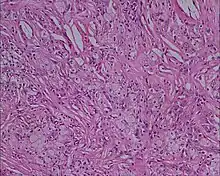

Xanthoma tuberosum

Xanthoma tuberosum (also known as tuberous xanthoma) is characterized by xanthomas located over the joints.[2]: 530